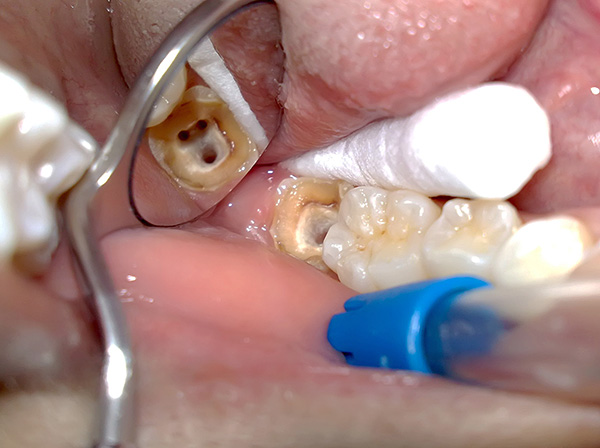

Se non fosse un dente del giudizio, qualsiasi dentista-terapeuta direbbe con fiducia che non è necessario rimuovere il dente, è sufficiente trattare i canali. Tuttavia, il dente del giudizio, a differenza degli altri, ha un numero imprevedibile di canali, le sue radici sono spesso piegate e l'accesso a un trattamento confortevole e di alta qualità è spesso difficile (specialmente quando si trattano gli otto superiori). Nelle condizioni di una normale clinica statale, non è sempre possibile trattare qualitativamente un tale dente e in futuro potrebbero sorgere complicazioni.

Allo stesso tempo, nelle cliniche dentali di livello aziendale, è possibile un trattamento endodontico di alta qualità con pulpite di quasi tutti, anche il dente del giudizio più insolito nella struttura - con il controllo dei processi sull'immagine, usando un microscopio dentale, un'apparecchiatura ad ultrasuoni, un localizzatore d'apice e altri dispositivi ausiliari. Tuttavia, il prezzo di questo servizio sarà considerevole.

Quando il processo infiammatorio nella camera della polpa va lontano, la polpa muore e stiamo già parlando della diagnosi di parodontite. In questo caso, il medico considera l'opportunità di preservare il dente dal punto di vista del rischio per la salute del paziente - a seconda della forma e dello stadio del processo, è possibile iniziare il trattamento dei canali in forme acute e nella parodontite fibrosa cronica.

Se stiamo parlando di granulomi, cistogranulomi, cisti, molto spesso il dente del giudizio viene rimosso "lontano dal peccato", sebbene a volte i metodi di conservazione dei denti possano essere selezionati in base alle indicazioni. Qui spetta al medico decidere e assumersi la responsabilità.

La foto sotto mostra il dente estratto con le cisti sulle radici: